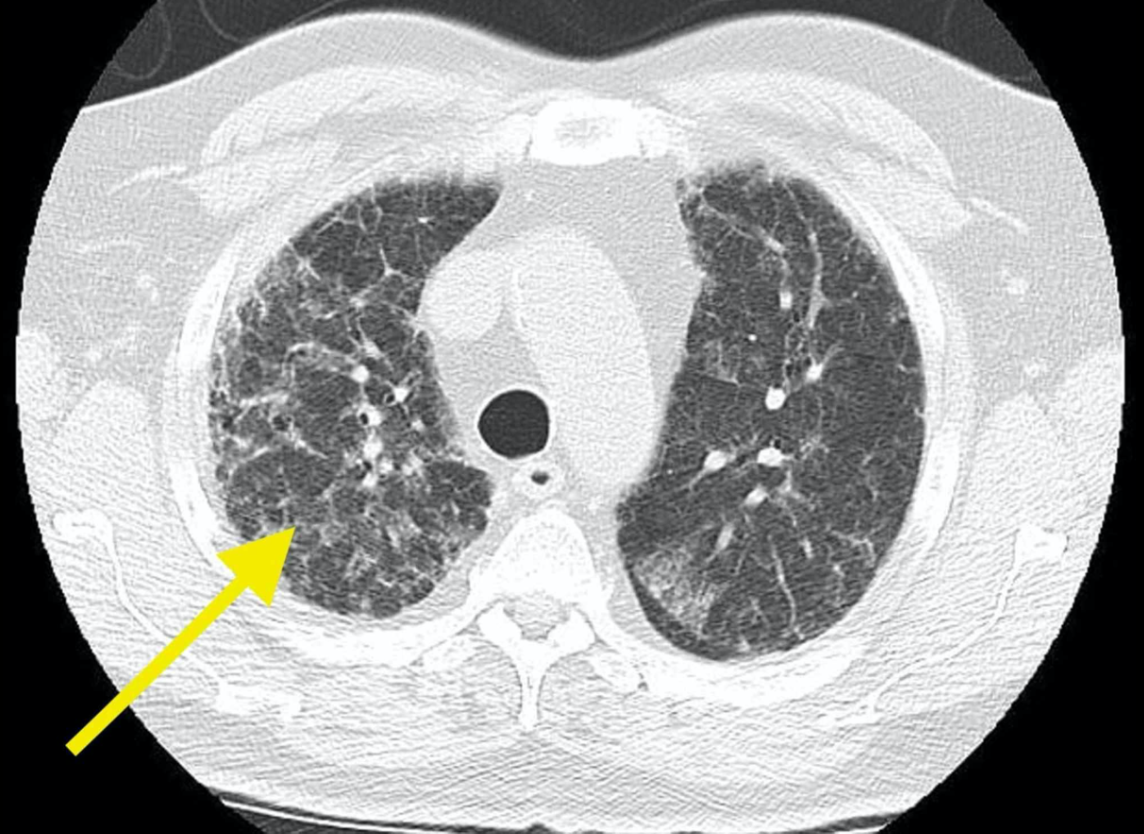

TC en enfisema

* Diagnóstica * Distingue distribución (centrolobulillar, panlobulillar o paraseptal) * Engrosamiento bronquial * Atrapamiento aire

EPOC centrolobulillar

EPOC panlobulillar

EPOC paraseptal